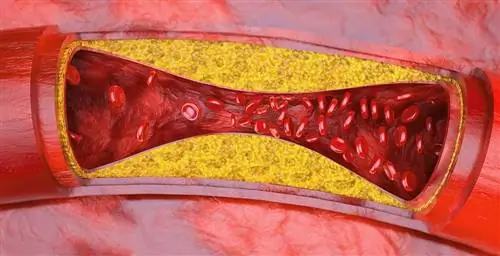

От него страдали даже ледниковый человек Эци, древние египтяне и бесчисленное множество других наших предков: атеросклероз, технически атеросклероз, - это действительно широко распространенное заболевание. Это происходит, когда холестерин и другие жиры крови накапливаются в стенках кровеносных сосудов, вызывая хроническое воспаление и повреждение стенок. В то же время это запускает клеточный суицид в клетках стенки сосуда. Со временем это приводит к утолщению стенок сосудов и ограничению кровотока.

Но, ингибируя каспазу-3, микроРНК защищает эндотелиальные клетки от гибели - по крайней мере, в нормальных условиях. Таким образом, miR-126-5p предотвращает повреждение, которое способствует возникновению артериосклероза в областях стенки сосуда, подверженных сильному стрессу. Эта ранее неизвестная функция этого фрагмента РНК вносит решающий вклад в защиту кровеносных сосудов и предотвращение кальцификации сосудов.

У пациентов с имеющейся сосудистой кальцификацией этот защитный механизм больше не работает должным образом. Как обнаружили ученые при исследовании больных сосудов, фермента клеточной гибели каспазы-3 особенно много в утолщении стенок артериосклеротических сосудов. В то же время в клеточном ядре этих уже поврежденных клеток можно обнаружить лишь небольшое количество защитных микроРНК.